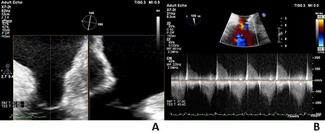

The authors describe 2 cases of patients with adult congenital heart disease with hypoplastic tricuspid valve annulus who were symptomatic from annular- and leaflet-level tricuspid stenosis.